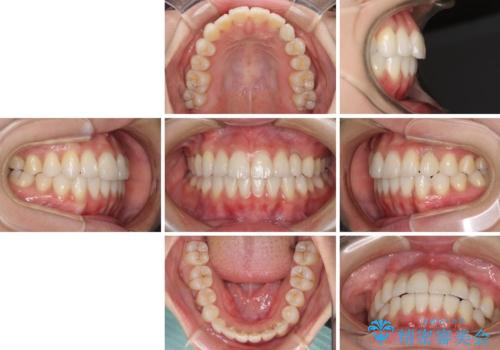

前歯のデコボコが強かったため、上の奥歯を後方に動かす量が多くなり、結果として2年以上の治療期間を擁することとなりました。

インプラント治療は当初の狙い通り、矯正治療期間中に行い、スムーズに処置を進めることができました。

歯並びが整ったことで治療前に認められた歯肉炎は全くなくなり、患者様には大変満足していただきました。